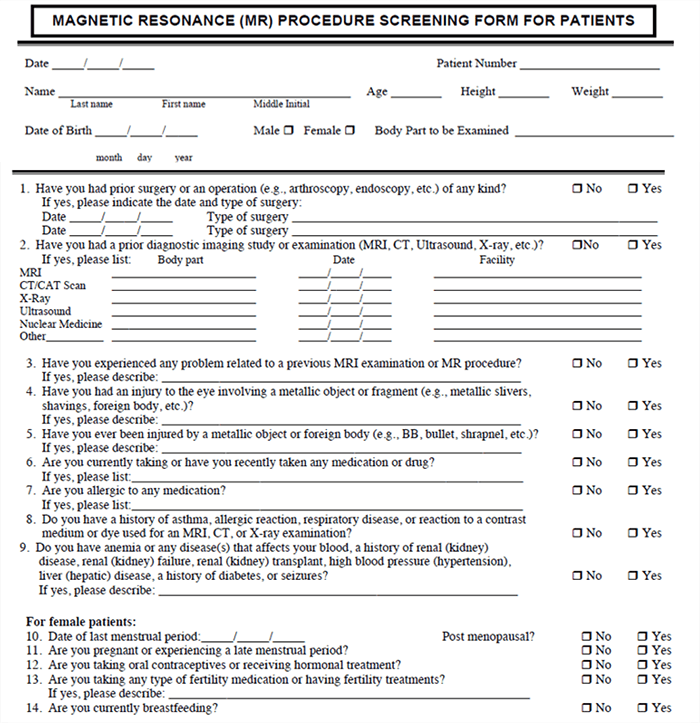

Typical Screening Form

When the scheduled date arrives, the patient arrives for their MRI and is given a more detailed screening form. Patients are usually required to sign these screening forms to attest to the correctness of the information. The screening form will repeat the questions done at pre-screening, but now this is a signed copy of those responses. Some questions on the screening form give information about other tests that have been done and information to help with the diagnosis of this exam.

The technologist then checks this screening form to make sure there is nothing that requires additional information is needed for clarity. If all goes well, everything had been taken care of at Pre-screening and the patient is ready to move on for the scan. Take a few moments to look at this example of a screening form and the types of questions that are asked.

This is the back of a typical screening form. Notice how many times and how many different ways some of the questions are asked. This is done to provide a thorough screening and to NOT have any issues with miscommunication or misunderstanding.

As an example, a patient might have a defibrillator in place, rather than the usual pacemaker/defibrillator. If the screening form was to only ask about pacemakers, a patient may think their defibrillator is ok. Some patients may feel that if something has been inside them for 20 years it is not relevant. And a patient with a bladder stimulator that is no longer functional may not find it important to reveal that it is in place because it no longer works.

A best safety practice would be to follow-up at the end by asking if the patient they have ever had any medical devices implanted in their body.